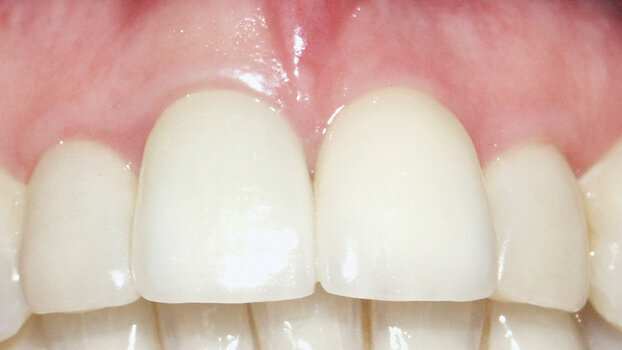

A Procera zirconium abutment was connected to the fixture (Fig. 8). The abutment screw was fastened down at the recommended torque of 35 Ncm. Procera porcelain crowns were fitted to both central incisors (Fig. 9).